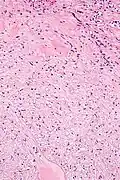

They consist of bland spindle-shaped or stellate-shaped cells in a loose stroma. Renal tubules may be entrapped.

Low mag. -

High mag.